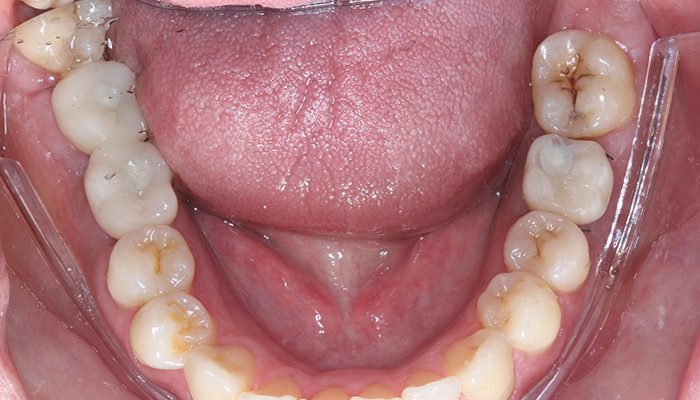

No dia seguinte a cirurgia, a paciente retornou para instalação das provisórias que foram desenhadas em software de desenho específico e impressas com a resina Voxelprint TEMP, cor A2 e cimentadas nos links Aikkon respectivos a cada componente utilizado. Assim foram instalados os provisórios e a paciente liberada. Foi realizada a remoção da sutura e fotos finais com 10 dias pós-opera tórios em que se contatou total adaptação e satisfação da paciente a nova condição.

21 | Remoção de sutura e controle 10 dias de pós-operatório – 36 vista vestibular

22 | Remoção de sutura e controle 10 dias de pós operatório – 46 e 47 vista vestibular.

23 | Remoção de sutura e controle 10 dias de pós operatório – Vista oclusal